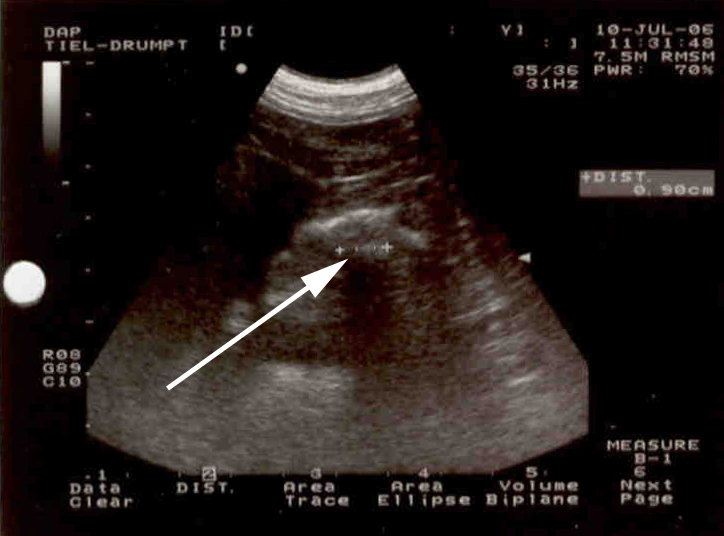

Met de echo zagen we ook een verdachte structuur:

Op basis van deze beelden hebben we besloten om Fanny te opereren.